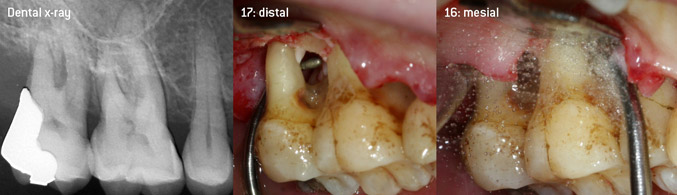

As initiators of the development of the new diamond-coated 3AP air scaler tip, the two dentists recognized the need for improvement of the handling restrictions of the commercially available diamond-coated tips, especially during furcation treatment and when working in tight intraosseous pockets. This should be possible for both non-surgical (Figure 2) and surgical (Figure 3) procedures.

(Fotos (Figures 2 -4): © Dr. Christian Graetz)

The aim was to develop a universally applicable tip in order to avoid time-consuming tip changes. In addition, it should be easier to use the new working tips in tight intraosseous pockets from distal and at the distal furcation entrance of maxillary molars, allowing more effective use of instruments as a result. This was achieved by employing an instrument curve with a larger diameter (Figure 1), which is highly advantageous for closed debridement on teeth with advanced attachment loss and involvement of furcation in particular (Figure 4).